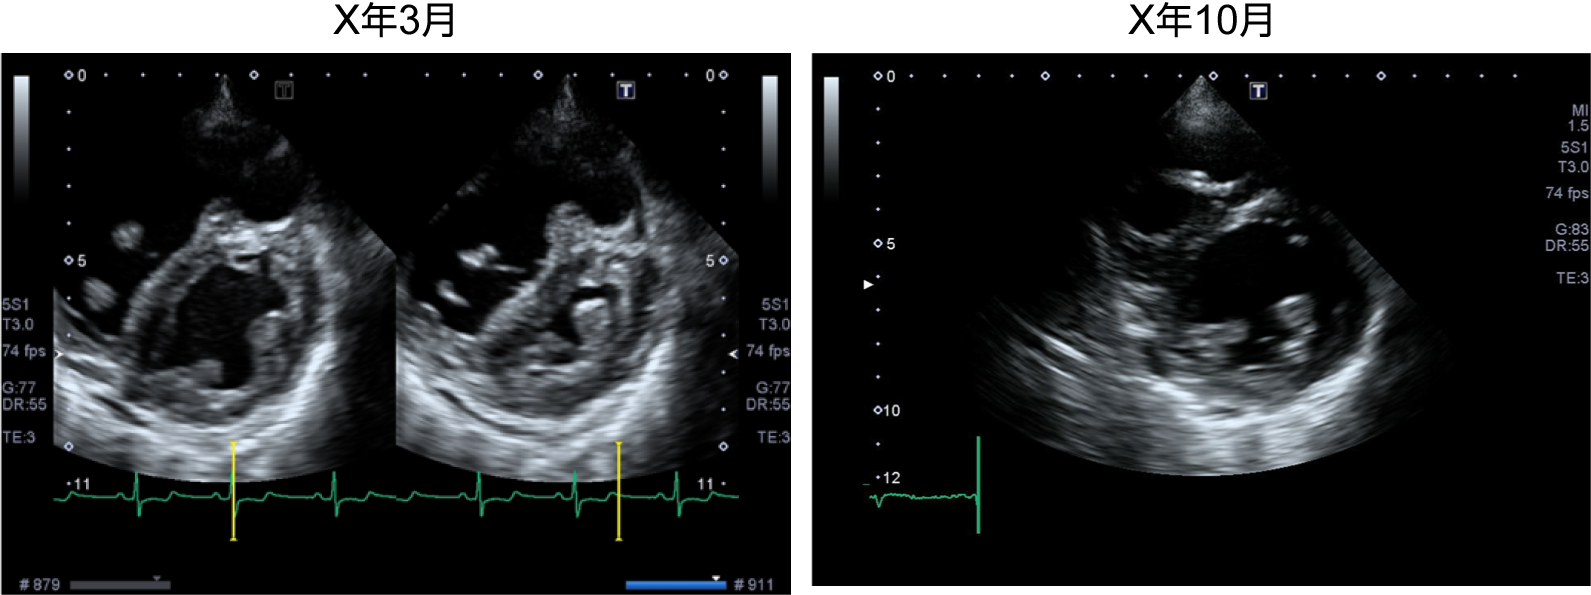

症例1:図1 治療前と治療後の胸部X線と心電図の変化

X線上心陰影は縮小し、心電図上も右室負荷所見が改善している。

症例1:図2 治療前と治療後の心エコー所見

心エコー上も右室の拡大および心室中隔の扁平化が改善している。